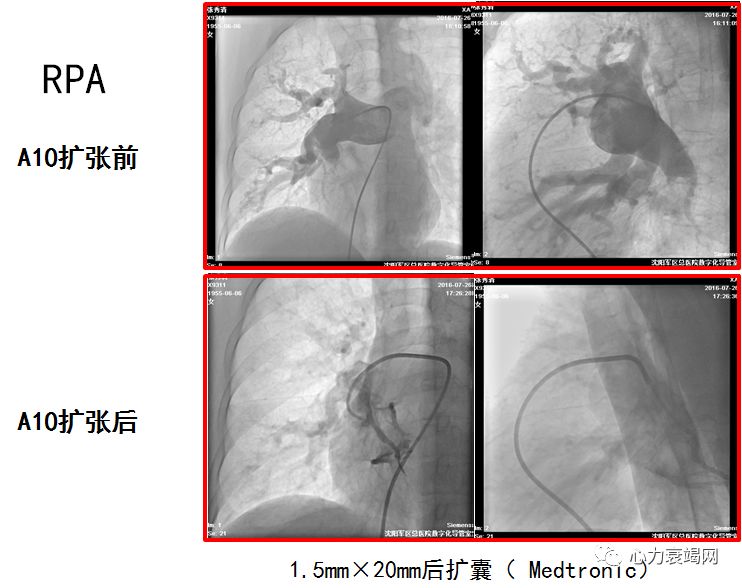

活动后胸闷、气短8年于2016年7月20日入院

确诊CTEPH 8年,拒绝肺动脉内膜剥脱术,服用华法林2年

球囊扩张术后肺动脉压力由120/48(72)mmHg降至90/32(51)mmHg